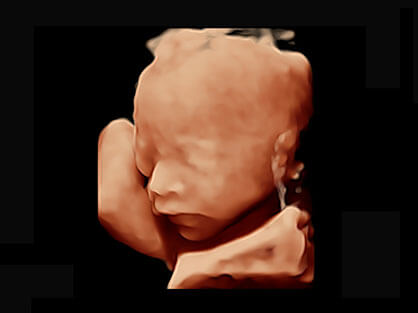

宽频带腹部凸阵探头和腹部容积探头、大角度腔内探头和腔内容积探头、独特的生殖专用曲柄探头,为妇产应用提供全面诊疗方案。

卵泡结构的自动识别和测量,可显示多组测量数据。

大角度腔内容积探头,可完整包络子宫及盆底结构,充分展示组织结构毗邻关系。